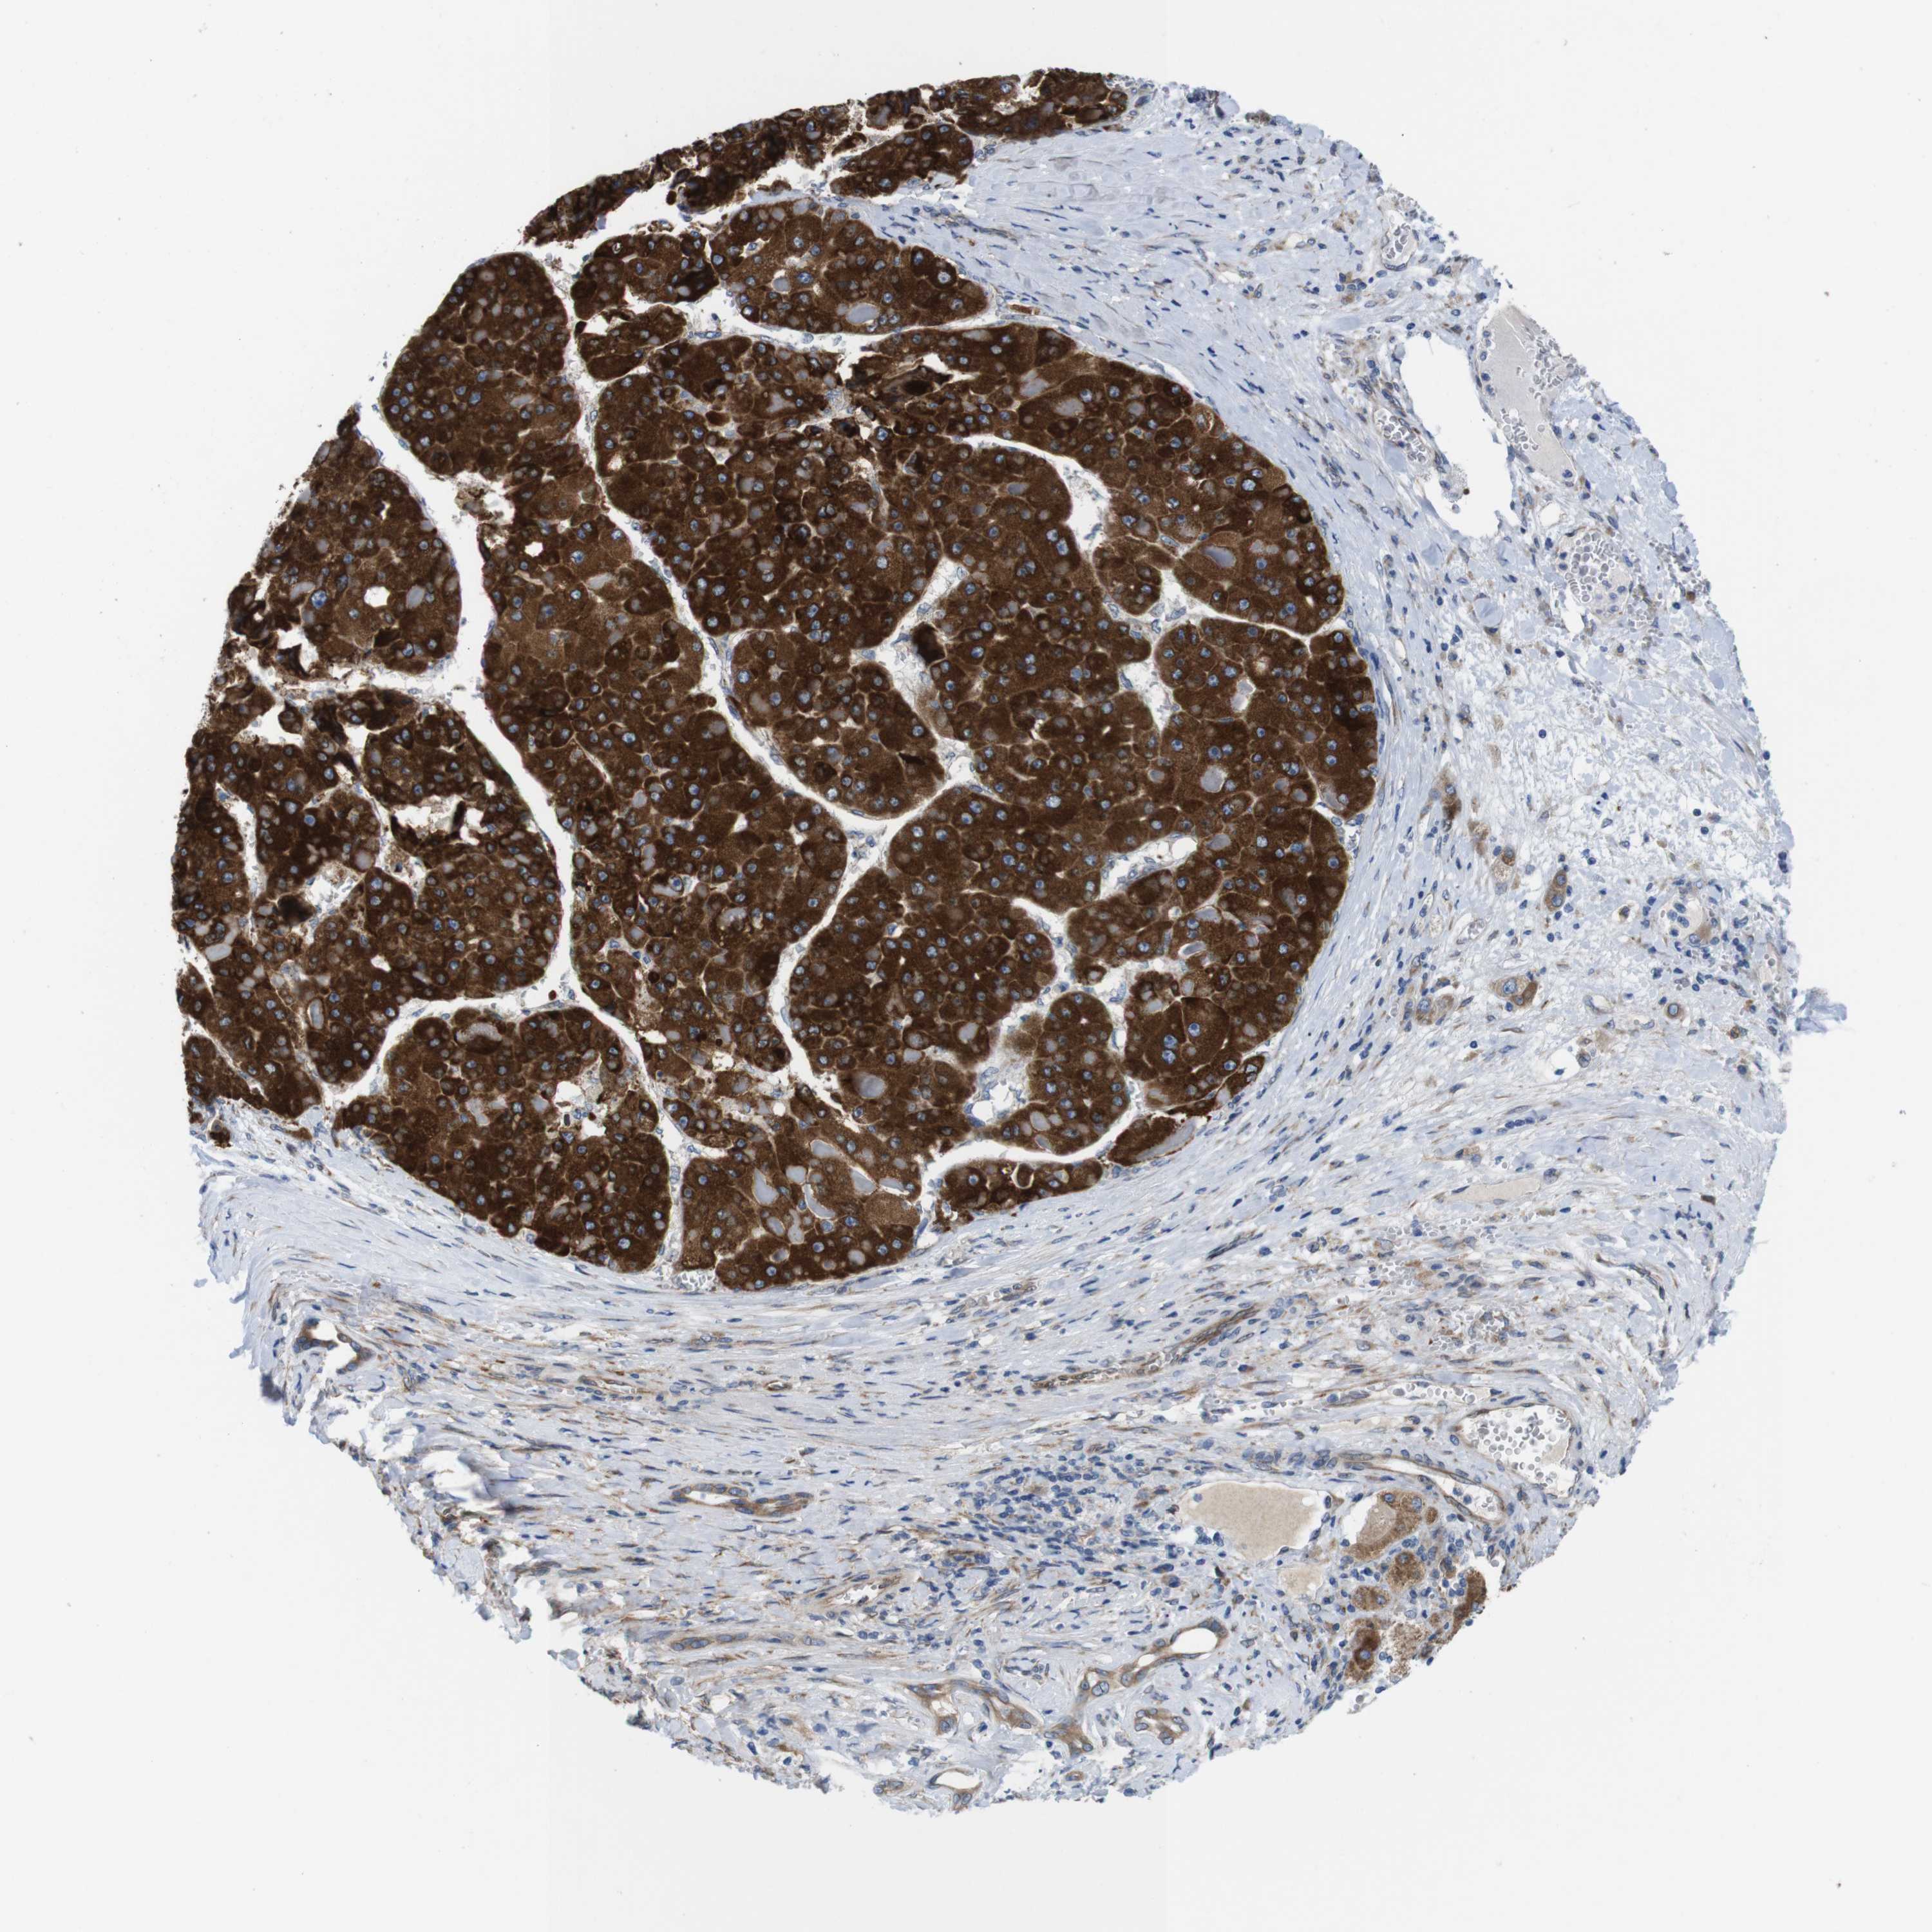

LIVER CANCER - Protein expressioni

A mouse-over function shows sample information and annotation data. Click on an image to view it in a full screen mode. Samples can be filtered based on level of antibody staining by selecting one or several of the following categories: high, medium, low and not detected. The assay and annotation is described here.

Note that samples used for immunohistochemistry by the Human Protein Atlas do not correspond to samples in the TCGA dataset.

Antibody stainingi

Antibody staining in the annotated cell types in the current human tissue is reported as not detected, low, medium, or high, based on conventional immunohistochemistry profiling in selected tissues. This score is based on the combination of the staining intensity and fraction of stained cells.

Each image is clickable and will lead to virtual microscopy that enables deeper exploration of all samples and also displays staining intensity scores, fraction scores and subcellular localization as well as patient and tissue information for each sample.

Antibody HPA014837

Staining

High

Medium

Low

Not detected

Intensity

Strong

Moderate

Weak

Negative

Quantity

>75%

75%-25%

<25%

None

Location

Nuclear

Cytoplasmic/membranous

Cytoplasmic/membranous,nuclear

Cholangiocarcinoma

Carcinoma, Hepatocellular, NOS